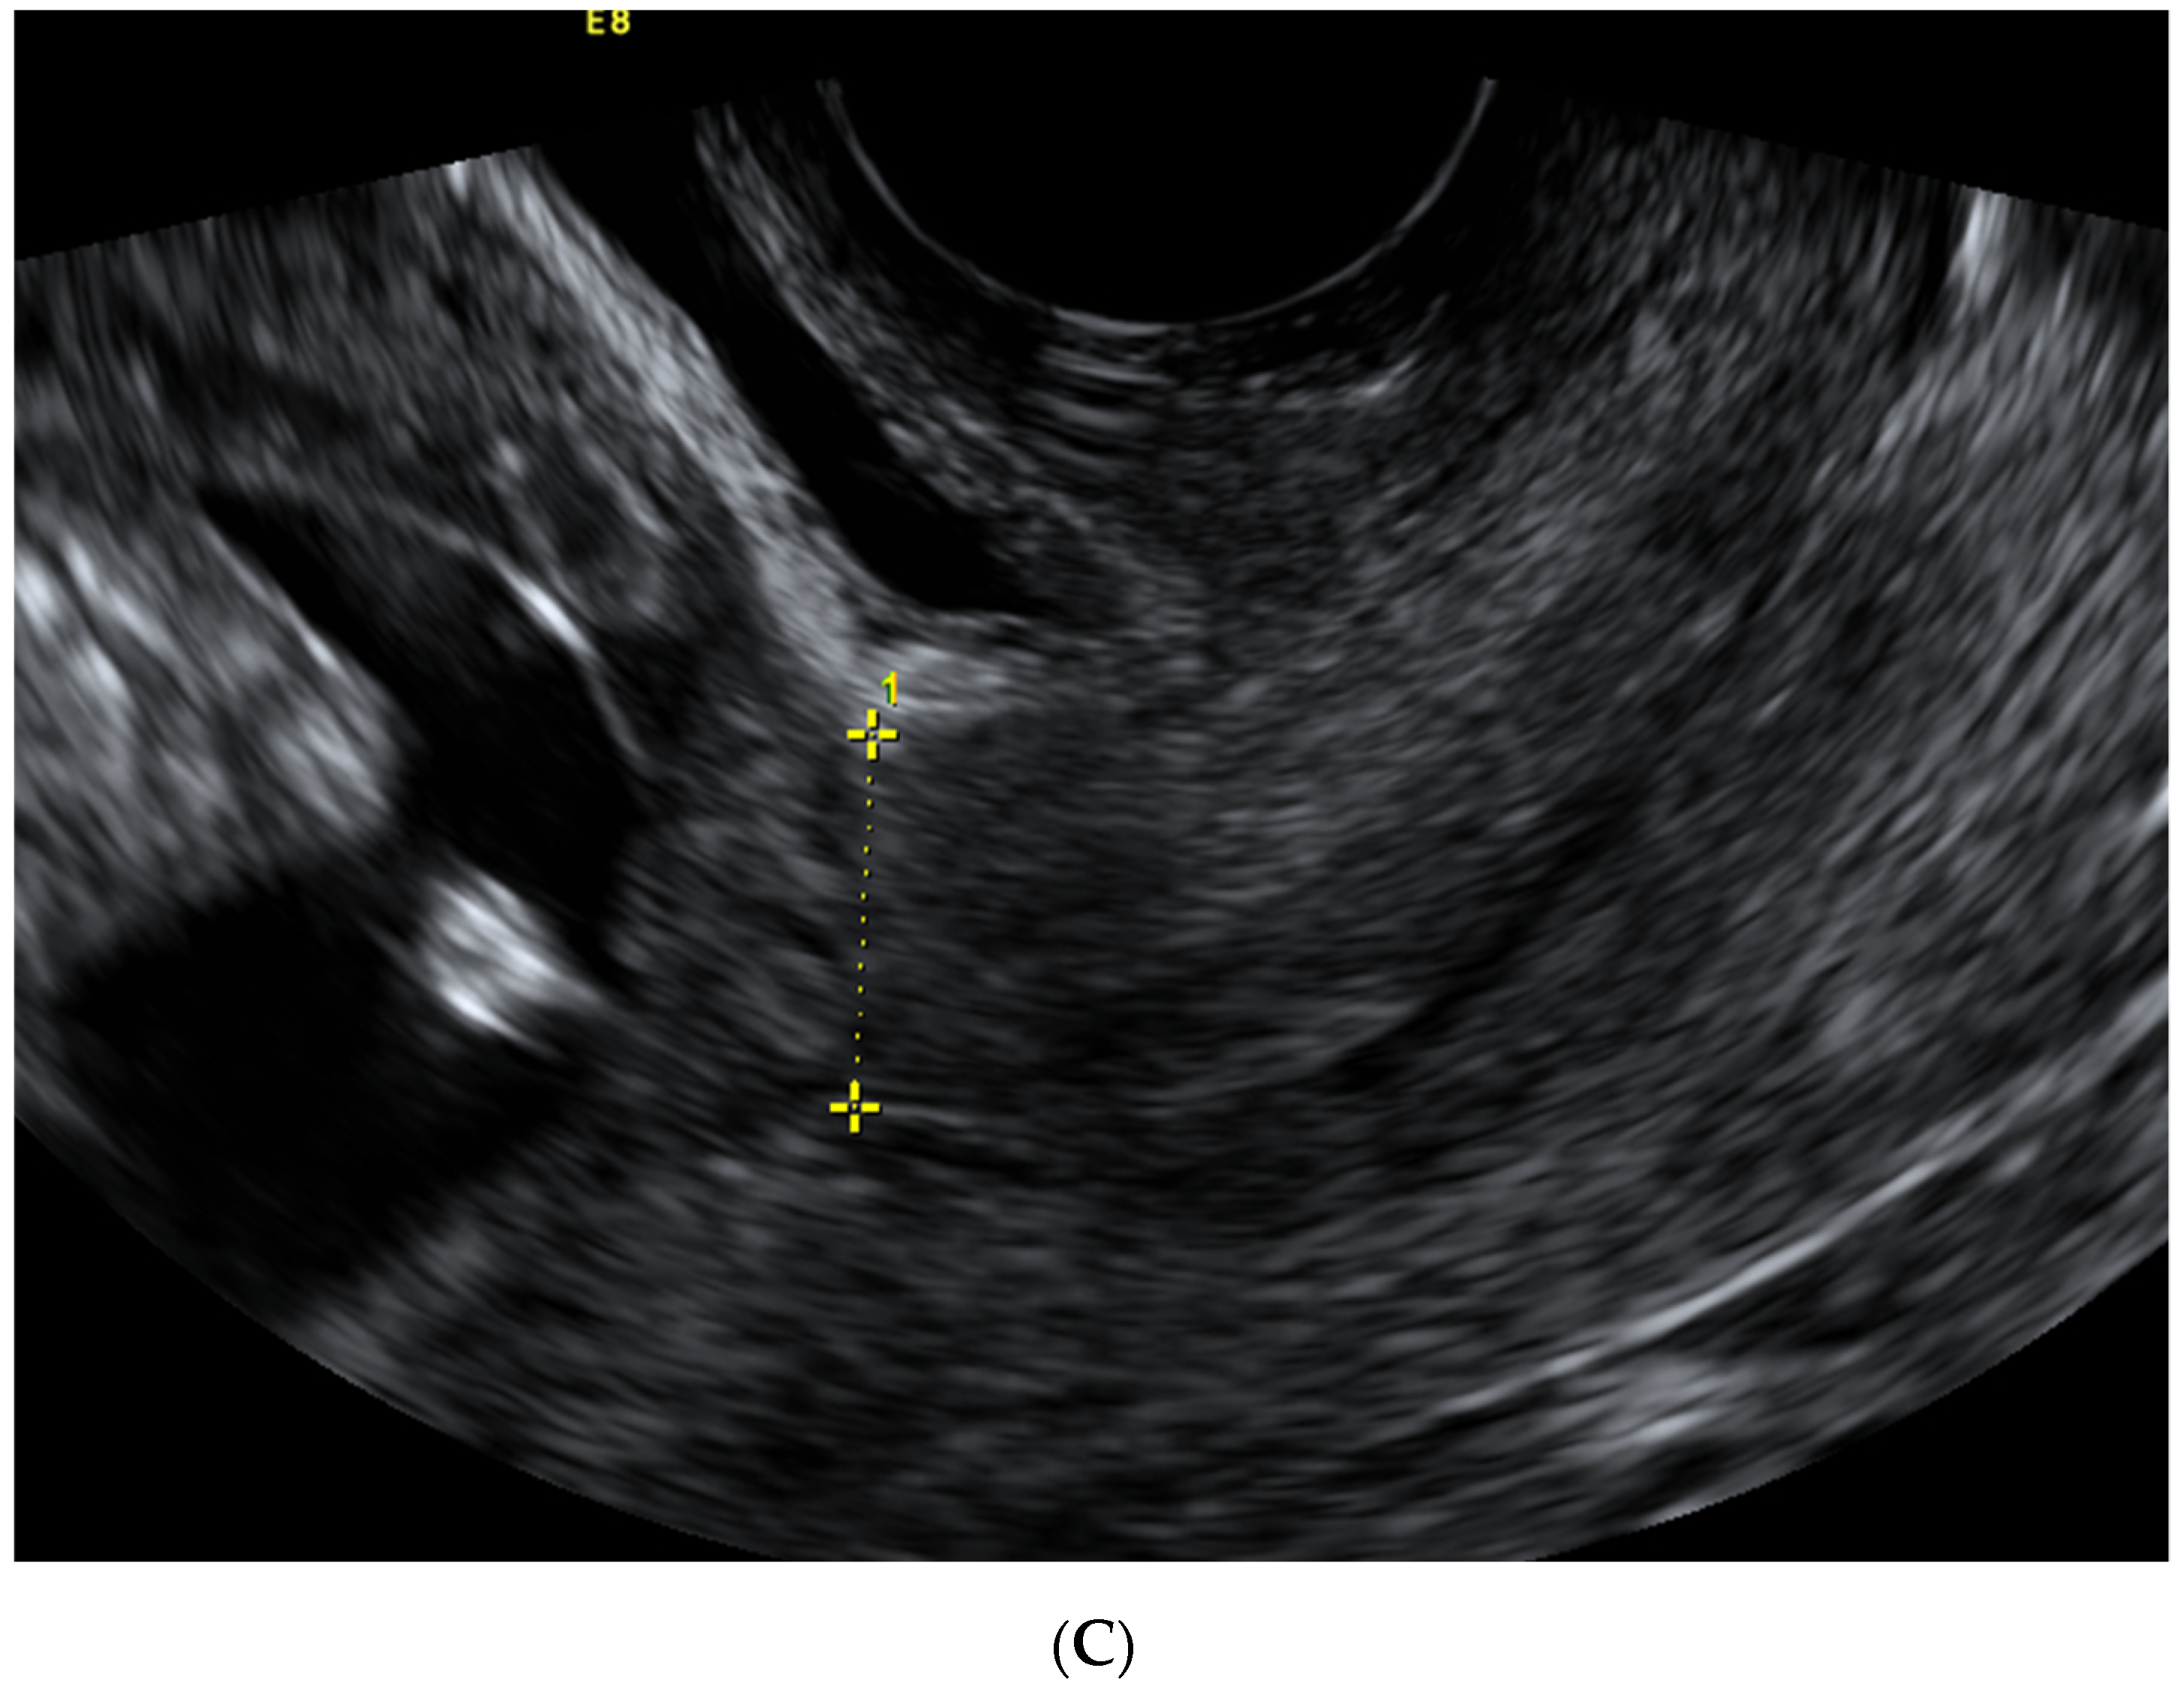

| Scar Characteristic (mm) | First Trimester Median (IQR)  | Second Trimester Median (IQR)  | Third Trimester Median (IQR)  |

|---|---|---|---|

| LUS thickness | - | 6.85 (5.2–9.1) | 4.0 (0.9–5.5) |

| Myometrial thickness | - | 3.85 (2.5–5.3) | 2.1 (1.7–2.7) |